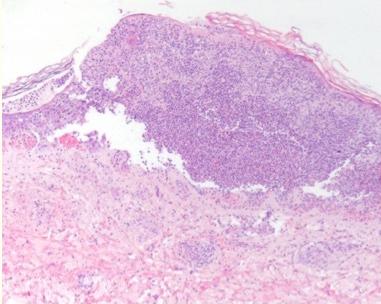

出院3周后,患者随诊诉*丸睾**疼痛15天,体重减轻(5KG)。体格检查发现腿部多发紫癜性病变伴溃疡、脓疱及溃烂(图1和2),手臂也发现瘀斑。皮肤活检显示角膜层脱落,角质形成细胞坏死和丰富的多形核细胞(图3),深部真皮及皮下动脉的多形核浸润伴血管炎的局灶性体征(图4),与结节性多动脉炎一致。患者接受泼尼松治疗,从60 mg开始,然后逐渐减少剂量,直到皮肤病变完全缓解。

图3HE染色显示角膜层脱落并伴有角质形成细胞坏死的区域